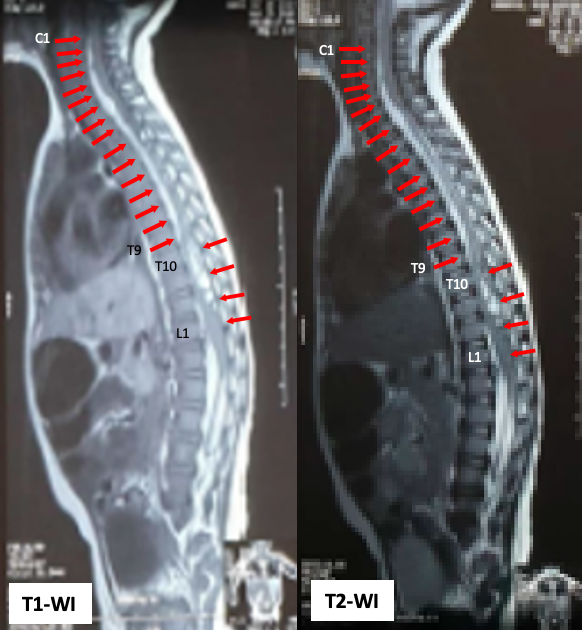

Case Presentation: A 15 month-old boy, with chief complain of difficulty in moving his leg and pain when walking, physical examination revealed a lower motor neuron lesion, laboratory showed a low factor VIII at 0.4% level, Magnetic Resonance Imaging (MRI) showed anterior and posterior displacement of the spinal cord due to the presence of the subacute subdural hematoma extending from 1st cervical to 1st lumbar spine. He assessed with inferior paraparesis caused by subacute spinal subdural hematoma due to hemophilia A. The patient’s condition was improved after received replacement therapy of factor VIII and proper laminectomy neurosurgery.

Figure 1. MRI of whole spine sagittal T1-weighted image and T2-weighted image revealed a subacute subdural hematoma extending from C1 to T9 on anterior aspect, then T10 to L1 on posterior aspect.